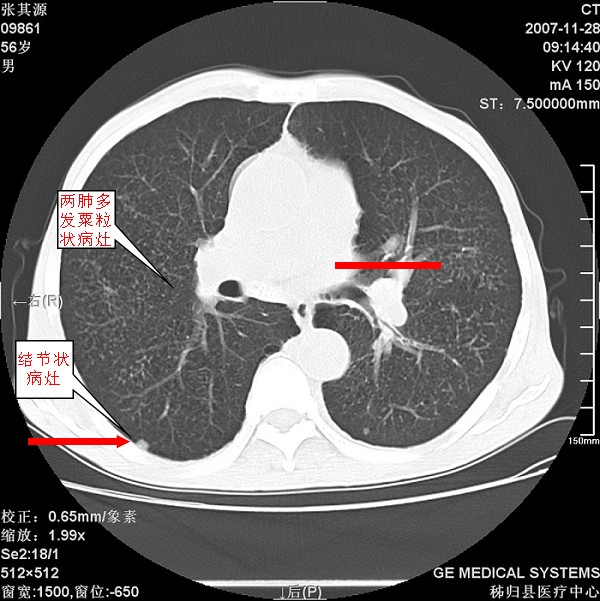

患者因阻塞性黄疸入院,发病前10天持续中等程度发烧.术前检查发现两肺弥漫性病变,请各位大虾会诊,除了考虑急性血源性肺结核外,还有其他什么疾病可能.

补充一下,该患者没有与尘肺相关职业史。请大家帮忙会诊一下,外科医生打算为其做胆总管肿瘤做手术的,现在在等我们的结果。谢谢各位了。

双肺多发粟粒样病灶,右肺胸膜下结节样病灶,气管前腔静脉后及隆突下均见肿大淋巴结,结合胆道肿瘤病史首先考虑转移。另外心影密度略低,时间格显示,是否有贫血?查明白再手术吧!